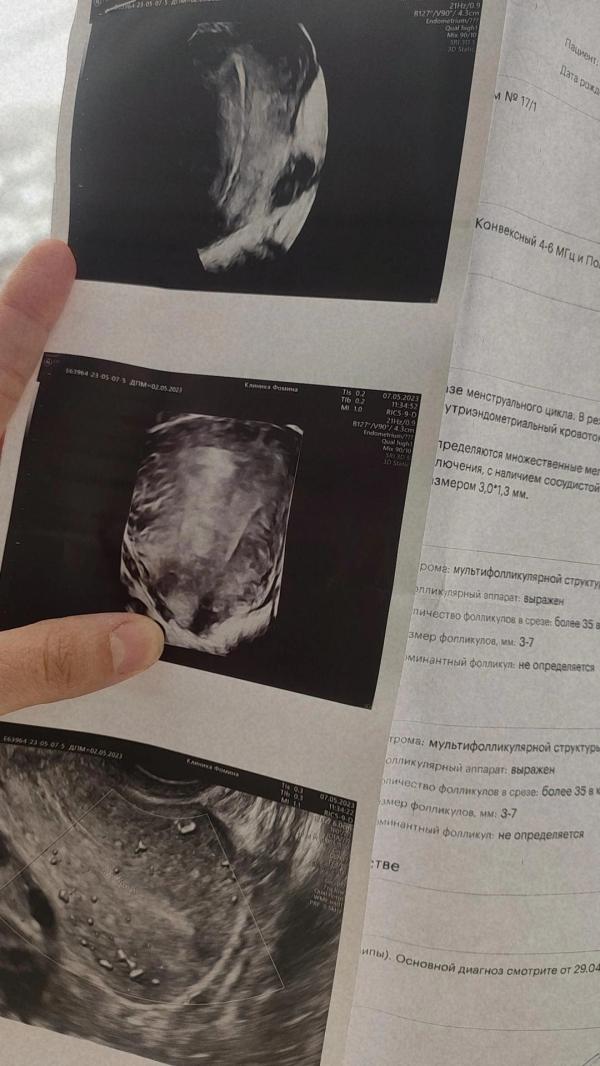

День менструального цикла: 6й день

М - Эхо толщиной, мм: 22

Нашли Эхографические признаки патологии эндометрия (полипы)

М - Эхо размер толщиной, мм : 4.0